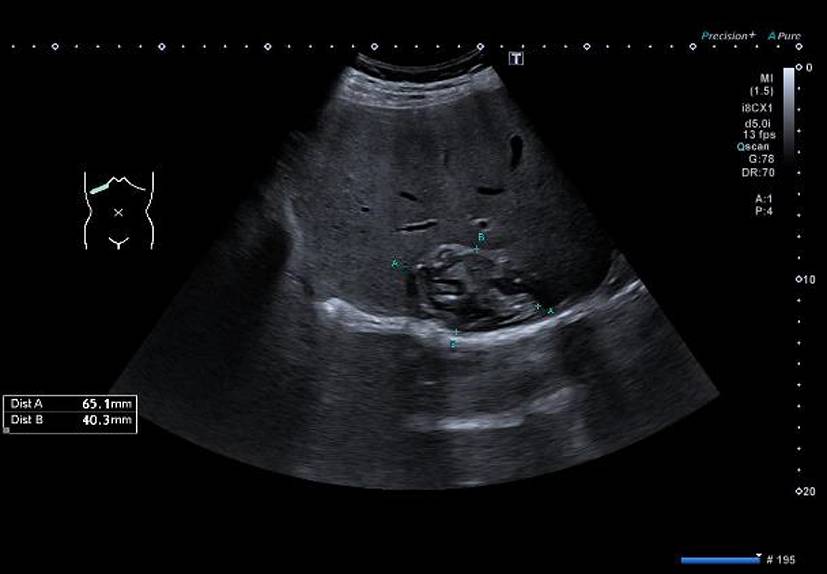

Die alveoläre Echinokokkose (AE) zeigt in der Bildgebung eine breite morphologische Variabilität und kann sowohl zystische als auch solide oder gemischt zystisch-solide Strukturen aufweisen (Abb. 1). Selbst für erfahrene Radiologen ist es oft schwierig, AE-Läsionen von malignen Erkrankungen wie intrahepatischem Cholangiokarzinom oder Lebermetastasen sowie von benignen Veränderungen wie Hämangiomen oder zystischer Echinokokkose zu unterscheiden. Zur Klassifizierung von AE-Läsionen wurden für Ultraschall, CT und MRT verschiedene deskriptive Systeme entwickelt [1315]. Diese haben aktuell vor allem in der Forschung eine Bedeutung. Im Ultraschall erscheint eine AE häufig als avaskulärer, gemischt echogener Tumor mit pseudozystischen oder verkalkten Anteilen, was gelegentlich Hämangiomen oder Metastasen ähneln kann [15]. Ein wichtiger Aspekt in der Bildgebung ist, dass der Nachweis von Verkalkungen nicht als Zeichen einer inaktiven Erkrankung gewertet werden darf [16].

Abb. 1

Verschiedene Präsentationen der alveolären Echinokokkose im Ultraschall. a AE, metastasenähnlich, b AE, hämangiomähnlich, c AE, primär zystisch, d AE, primär solide